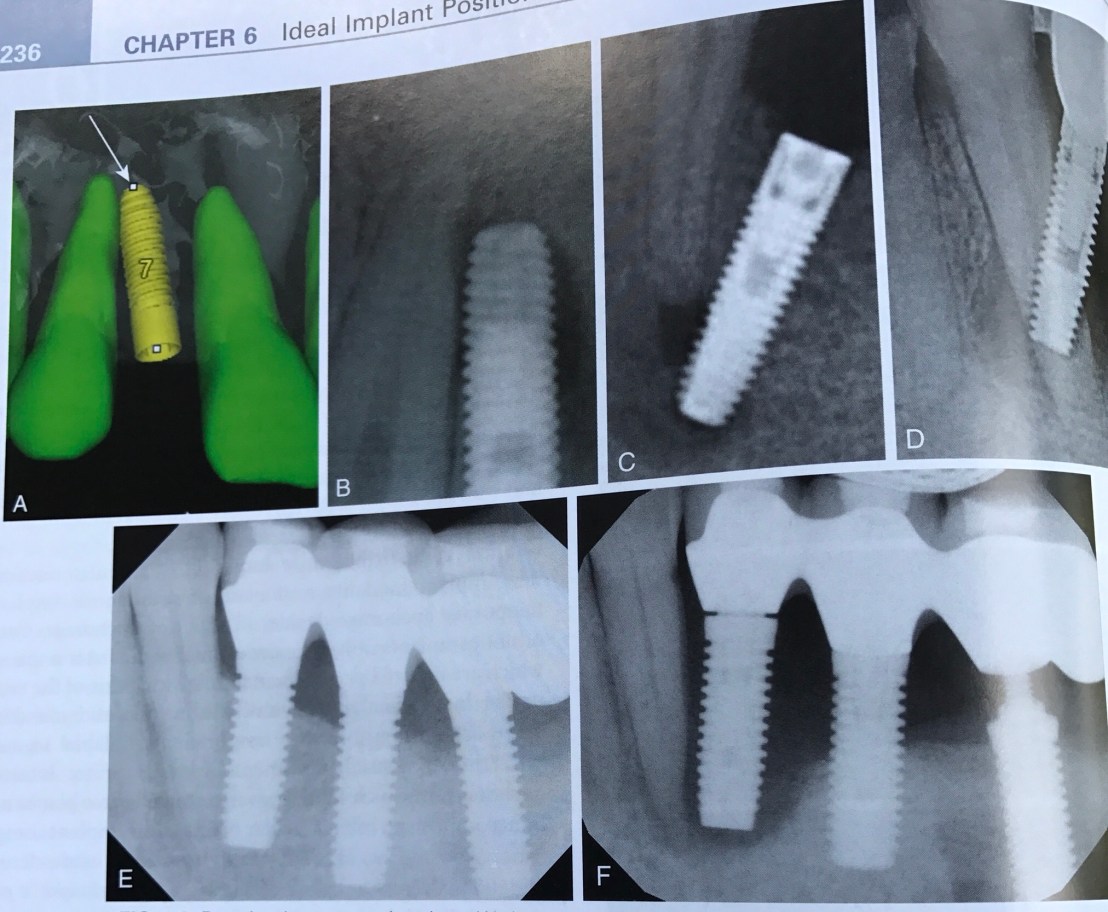

บทที่ 6 ความผิดพลาดจากการวางตำแหน่ง Implant

หรือพูดอีกอย่างคือ การวางตำแหน่งที่ถูกเหมือนการติดกระดุมเม็ดแรกถูกนั่นเองครับ สมมติถ้าเราวางตำแหน่งได้ไม่ถูก จะทำให้ต้อง compromise ตามมาทั้งในแง่ Pros, Perio และการคงอยู่ระยะยาวของ Implant เอง

รูปนี้ให้สังเกตระดับ Implant เทียบกับ CEJ ของฟันธรรมชาติข้างเคียงครับ

รูป A คือการวางตำแหน่งลึกลงไป 4 มม. เทียบกับ CEJ

รูป B คือวางตำแหน่ง Implant ลึกลงไป 2 มม. เทียบกับ CEJ

B คือ Ideal กว่า A เพราะ A จะเกิด Perio ได้มากกว่า (Bone loss ทำให้เกิด probing depth มากกว่า และ Anaerobe bacteria colonize ได้ดีกว่า

แสดง Implant ที่ฝังตื้นเกินไป (สังเกตระดับ CEJ)

รูป B,C คือ Screw หักครับ

ส่วนรูป D คือปัญหาในการสร้าง crown ให้ได้ Emergence profile ที่ดี (เพราะมี space ให้ Clinical crown น้อยเกินไป)